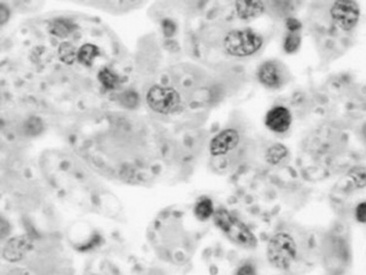

Histoplasmosis is caused by the saprophytic, dimorphic fungus H. capsulatum, which is most prevalent in moist soil containing bird or bat waste. Yeast organisms are 2 to 4 μm in diameter, with a thin clear halo surrounding a round or crescent-shaped basophilic cytoplasm (Fig. 31-24). Histoplasmosis has been reported in less than 10 equine cases,330 and thus horses are considered to be relatively resistant to disease. H. capsulatum may occur in an enteric, pulmonary, or disseminated form.330H. capsulatum was identified in pulmonary granulomas in a horse dying of chronic Yersinia colitis372 and in another horse with intestinal salmonellosis.373 It has also been associated with abortions and severe granulomatous pneumonia in neonatal foals (Fig. 31-25) and a yearling.374 Successful treatment with amphotericin B was reported in a filly with pulmonary histoplasmosis diagnosed by cytologic identification of the organism on a tracheal wash smear and from a lung aspirate.330

image

Fig. 31-24 Photomicrograph of tissue infiltrated by activated macrophages containing usually multiple yeasts of Histoplasma species. These yeasts characteristically measure approximately 2 to 4 μm and appear as structures with a basophilic center and clear halo. (Hemotoxylin and eosin stain, ×40.)

Courtesy Arno Wünschmann, University of Minnesota, St. Paul, Minn.